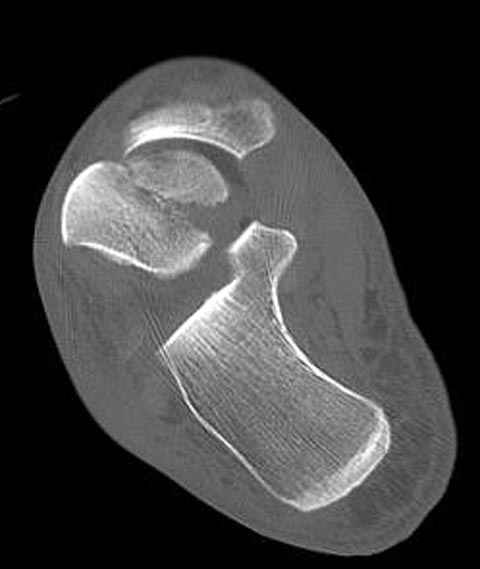

Уважаемые участники русского Ортофорума, поздравляю всех со всеми прошедшими праздниками: Новым годом, Рождеством, Hanukkah, Kwanzaa, желаю участникам всего наилучшего и здоровья.Повреждение таранной кости.Больной 81г автоавария, повреждение таранной кости, здесь снимки. Какие рекомендации?Djoldas Kuldjanov, MDDepartment of Orthopedic SurgerySt. Louis University Medical Center

В декабре у меня был пациент с политравмой и аналогичным повреждением тарана с подвывихом в таранно- ладьевидном суставе, единственное отличие - отломок головки тарана был меньше по размеру и фрагментирован, поэтому его фиксация была невозможна.

Для доступа к задне-медиальному суставному фрагменту я выполнил косую остеотомию внутренней лодыжки у её основания -получается хороший доступ к голеностопу, адекватный обзор и возможность восстановить суставную поверхность. фрагмент фиксировал двумя 3,5 мм спонгиозными винтами с неполной резьбой, *утопив* головки винтов в кость. Аналогичная фиксация и двумя тягловыми винтами и внутренней лодыжки. \в качестве альтернативы для

фиксации фрагмента тарана можно было бы использовать и герберт винты, но по организационным причинам :-(( набора не оказалось под рукой).

Повторный осмотр назначил через 2 мес с момента операции. Отдаленных наблюдений такого подхода у меня нет( достаточно редкий тип повреждений таранаHawkins II), но наблюдения в ближайшем послеоперационном периоде выглядели вполне прилично, на мой взгляд.

Вдогонку по поводу перелома таранной кости, больная 81, не страдает диабетом, перелом закрытый, в первый же день поступления ограничились временным наружным фиксатором (как на снимке).

Примеры на снимке...